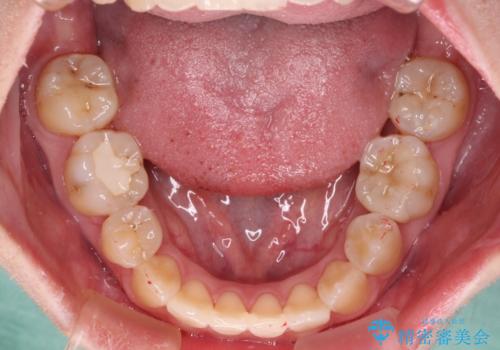

- 奥歯が痛いとのことで来院された患者様です。

上顎親知らず周辺の炎症と、神経組織の失活した歯の炎症による痛みが認められたため、親知らずの抜歯と根管治療を行いました。

根管治療を行った歯はクラウンによる補綴治療が必要となりますが、高校生の頃に行った矯正治療の後戻りも気になるとのことで、補綴治療を行う前に矯正治療を行うこととしました。

後戻りは軽度であり、インビザラインにて歯列を整え、その後にオールセラミッククラウンにて補綴治療を行うこととしました。

ご家庭やお仕事の都合で通院が途絶えた時期があり、治療は長期間となりましたが、無事に終えることができました。